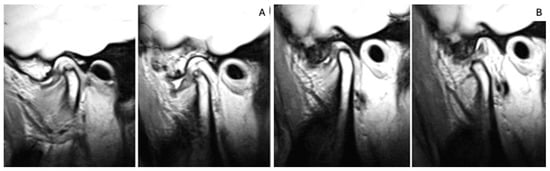

2.5. MRI Analysis